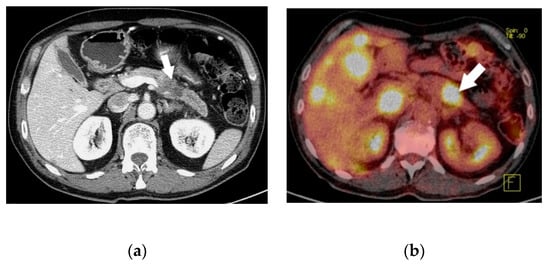

Among 239 patients with a histologically confirmed pNET observed in our unit during the study period, seven (2.9%) patients had a 5-HT-secreting pNET. The study population consisted of four men and three women, with a median age of 64 (range 38–69) years. Only two patients had symptoms related to a carcinoid syndrome with flushing and diarrhoea (Figure 1); all the others presented with a non-functioning pNET. The leading presenting symptom was weight loss in three (43%) patients, and two (29%) patients complained about abdominal pain (Figure 2). One patient had a cervical lymphadenopathy, and another presented with jaundice and ascites due to portal vein thrombosis (Figure 3).

Figure 2. Computed tomography scan 2 (a) and 18F-FDG positron emission tomography/CT 2 (b) showing a pancreatic neuroendocrine tumor in the body of the pancreas (white arrow) with multiple liver metastases (case n.7).